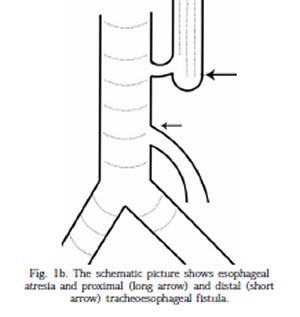

What is esophageal atresia?

congenital atresia of the esophagus

What causes esophageal atresia?

failure of recanalization of the GIT

a blind end tube is result

What is present in most cases of esophageal atresia?

tracheo-esophageal fistula

What percent of esophageal atresia have a tracheo-esophageal fistula present?

90%

What is the sonographic appearance of esophageal atresia?

polyhydramnios

stomach usually not identified

tracheo-esophageal fistula